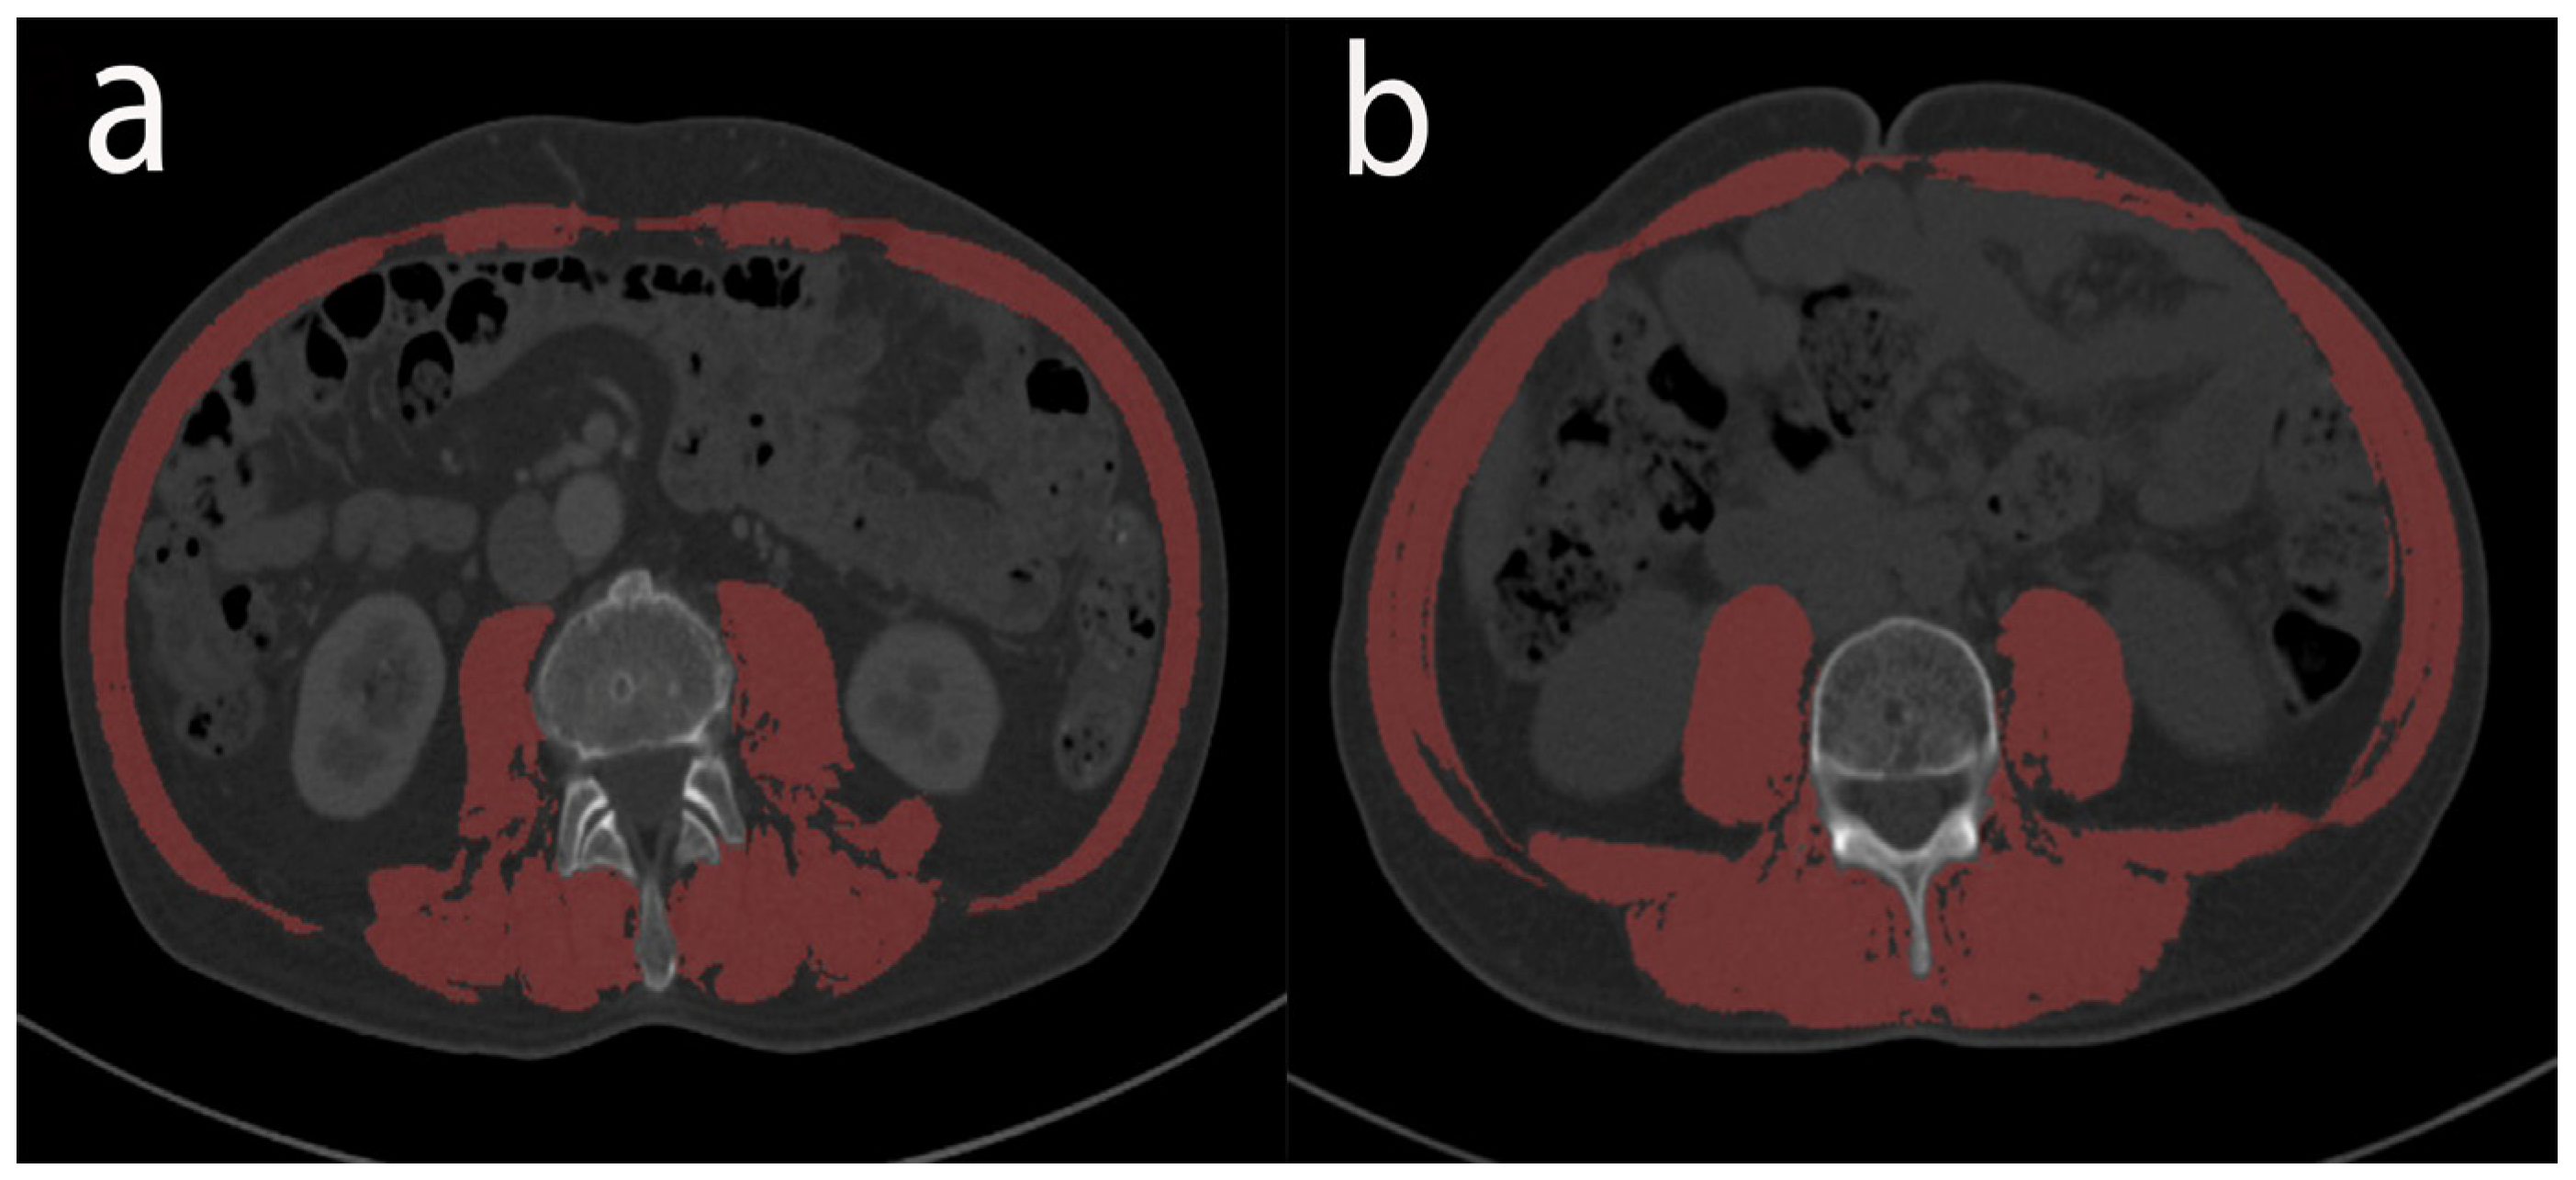

2.4. Nutritional and Inflammation Assessment